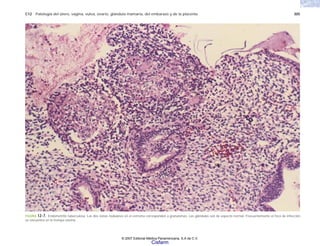

TABLA 8-5 Virus oncogénicos.

© 2007 Editorial Médica Panamericana, S.A de C.V.